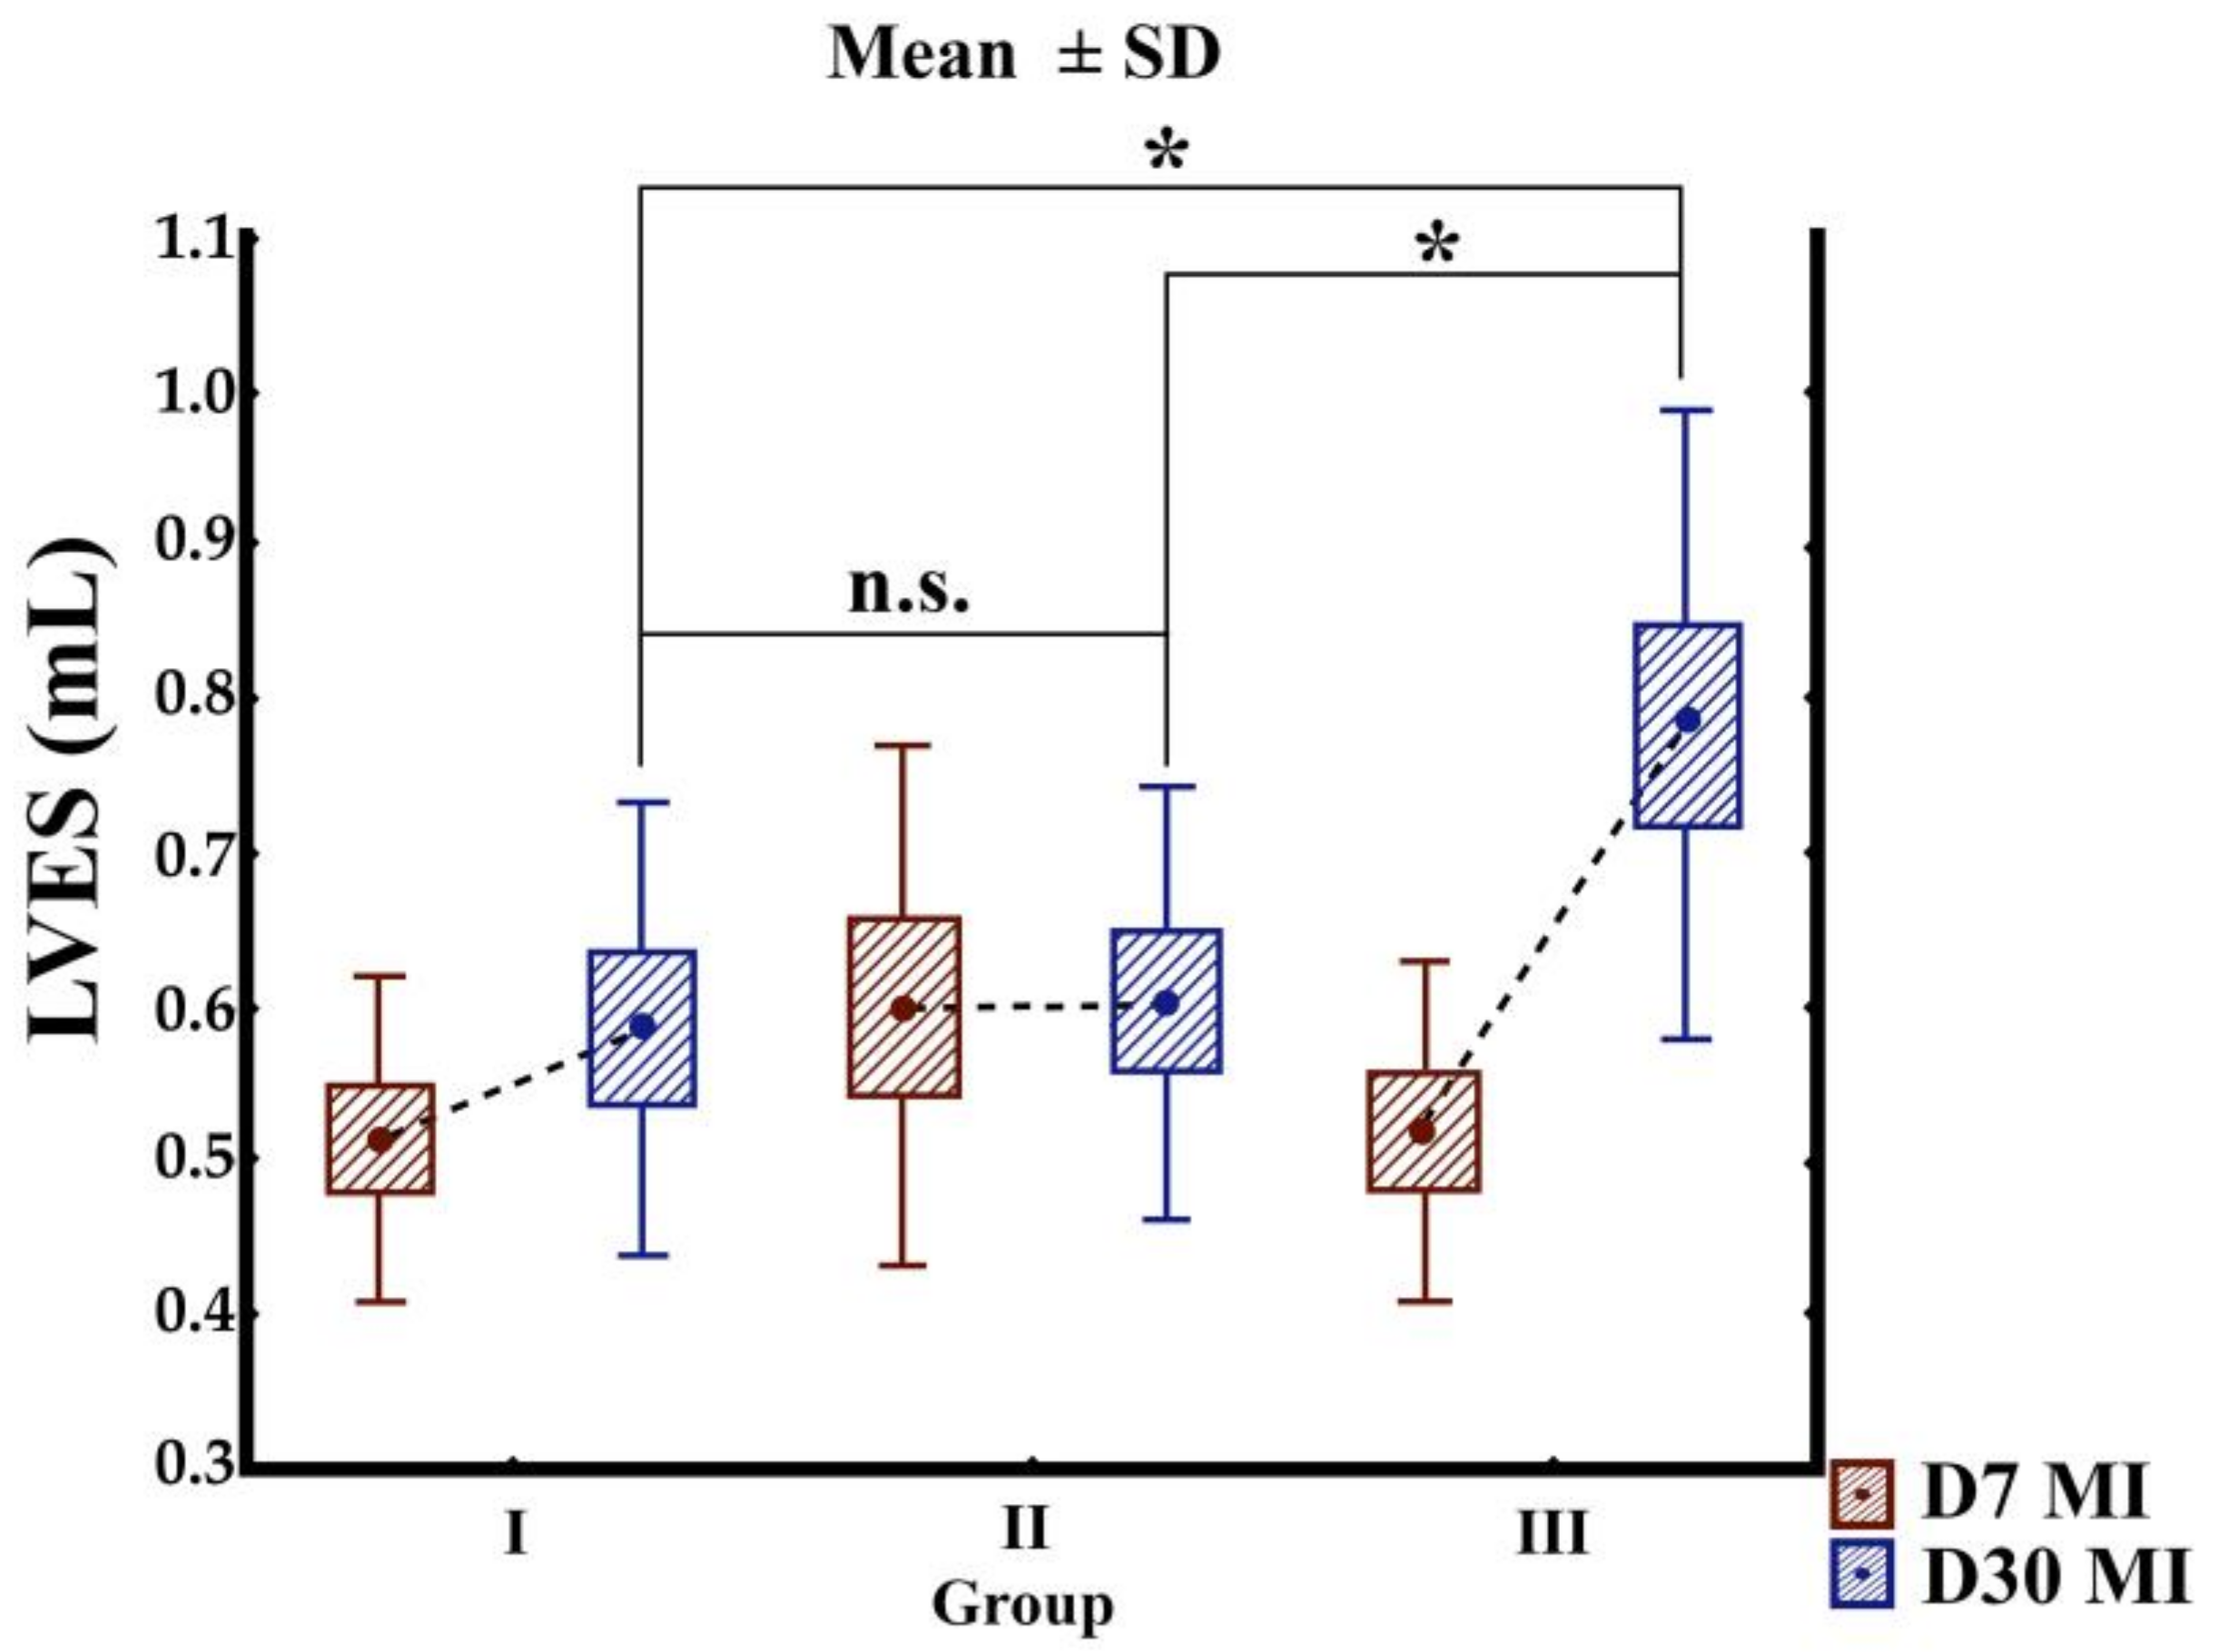

3.2. Echocardiographic Findings

| Variable | Group | D7 | D30 | p-Value (D7 vs. D30) |

|---|---|---|---|---|

| LVEF (%) | I | 28.21 ± 5.07 | 32.72 ± 8.62 | 0.316 |

| II | 22.79 ± 5.80 | 26.74 ± 4.92 | 0.065 | |

| III | 27.37 ± 8.40 | 27.92 ± 9.77 | 0.865 | |

| LVES (mL) | I | 0.509 ± 0.106 | 0.582 ± 0.149 | 0.241 |

| II | 0.596 ± 0.171 | 0.598 ± 0.141 | 0.982 | |

| III | 0.514 ± 0.112 | 0.780 ± 0.206 | 0.001 * | |

| LVED(mL) | I | 0.718 ± 0.170 | 0.848 ± 0.149 | 0.326 |

| II | 0.747 ± 0.196 | 0.768 ± 0.158 | 0.043 | |

| III | 0.698 ± 0.102 | 1.056 ± 0.183 | 0.004 * |